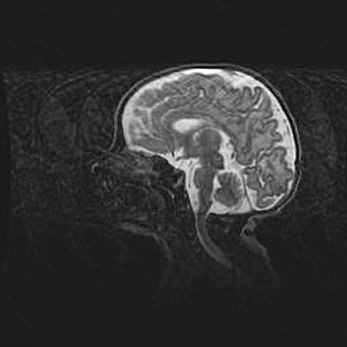

Мальформация Денди-Уокера. Киста задней черепной ямки.

Агенезия мозолистого тела.

Возраст: 2,5 месяца

Вес: 2420 г

Пол: женский

Окружность головы: 37 см

Срок гестации: 32 недели

Мальформация Денди—Уокера — редкий вид патологии ЦНС, представляющий собой врожденный порок развития каудального отдела ствола и червя мозжечка, ведущий к неполному раскрытию срединной (Мажанди) и латеральных (Лушка) апертур IV желудочка мозга. Для этогно синдрома характерна триада симптомов: гипотрофия червя мозжечка и/или полушарий мозжечка, кисты задней черепной ямки, гидроцефалия различной степени. В 70% случаев порок сочетается и с другими аномалиями головного мозга, в частности с агенезией мозолистого тела.